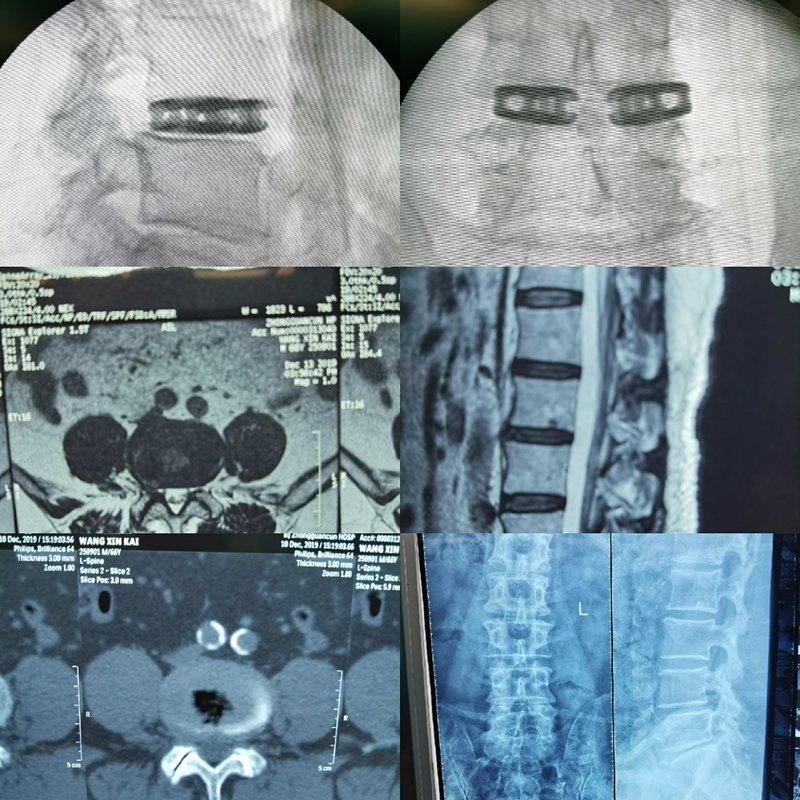

上次说到小编采访了椎间孔镜技术下双枚CAGE腰椎间撑开融合术(WLIF)创始人王文教授,他详细的介绍了这项技术以及老乔为什么要采用该技术来完成手术。那么我们这次接着看一下这种新型融合术的优势又是什么呢?让我们听一下教授是怎么说的。请看文章最下面第一个视频!在这里我们不得不提一下传统开放融合术,开放融合手术存在创伤大,风险系数高,加速临近阶段退变,术后遗留腰疼等问题。下面这几张图就是开放融合手术,大家做好准备了吗?请注意,前方高能预警!!!画风一转,上面两个是老乔手术后的片子,大家可以清晰的看到椎间有两个膨胀式支撑块(CAGE),据教授自己说他还是很满意这台手术的,这两个CAGE的位置也都很好,相比开放手术的惨不忍睹的创面,本台手术的创口只有分别两个1.5cm,简直幸福不要来的太快,小编的疑惑是腰部两个分别只有1.5cm的开口是怎么放进这两个东西的呢?相信和小编有同样疑惑的人不在少数。那么我们请王教授再来为我们解答一下。请看文章最下面第二个视频!大家看了这个动画演示就更明白了请看文章最下面第三个视频!我们将持续关注王文教授和他的这项创新技术,请看系列文章第3集。王文主任开放门诊时间为每周二上午。提前预约无需挂号便可以享受绿色通道,直接接受专家的诊治医院地址: 北京海淀区中关村南大街十二号中科院中关村医院急诊7楼脊柱微创科。

看过前两集之后呢,想必大家已经对这项技术已经有一个大概的了解了,知道了这项技术的适应症也知道了它的优势,还知道了两个膨胀融合物CAGE是怎么通过1.5cm的创口放进老乔体内的,那么随即问题又来了,相信和小编有同样想法的吃瓜群众绝对不算少数,就是既然这两个CAGE放进去了,那么它们会不会跑出来呢?听听王教授是这么回答的。请看文章最下面第一个视频!下面是小编向王教授要来的CAGE图片,这些可都是国外进口的最先进的医疗设备,大家可以清晰的看到它们的结构,锯齿状的CAGE感觉就跟带着倒刺一样呢。再用王教授的话说,就是膨胀螺丝的原理加上这样的结构,相信放进去以后一定很牢固。现在我们再把视线回到老乔身上,经过王教授手术的老乔到底恢复的怎么样呢?术前和术后各方面的对比到底如何呢?下面发的图是老乔术前的片子,据王教授说老乔因为2017年脊髓型颈椎病做的开放手术,术后仍感腰酸、腿痛、腿麻、无力,拖着腿走路等症状。下面这是老乔术后的片子,据教授说椎间隙狭窄,滑脱,椎间盘突出都得以纠正。好了,我们再来看一下老乔术后一个月的恢复情况请看文章最下面第二个视频!(视频中白衣服的就是老乔)和他自己的一些真实体会,小编在这里要感谢一下王文教授病友群群主沧海笑的支持。(视频和截图均出自病友群)最后小编奉献上王教授给老乔做的这台完整手术视频供大家欣赏,一台万人观摩的创新型微创融合手术。下一集小编会继续关注王文教授和他的这项新型技术的发展,病人老乔的后续恢复情况也会呈现给大家。敬请期待!王文主任开放门诊时间为每周二上午。提前预约无需挂号便可以享受绿色通道,直接接受专家的诊治医院地址: 北京海淀区中关村南大街十二号中科院中关村医院急诊7楼脊柱微创科。